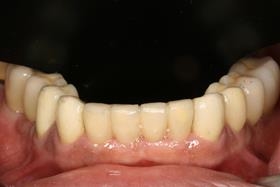

全口植牙重建

經過一年多牙周病治療與人工植牙重建病患恢復了完整的牙齒。